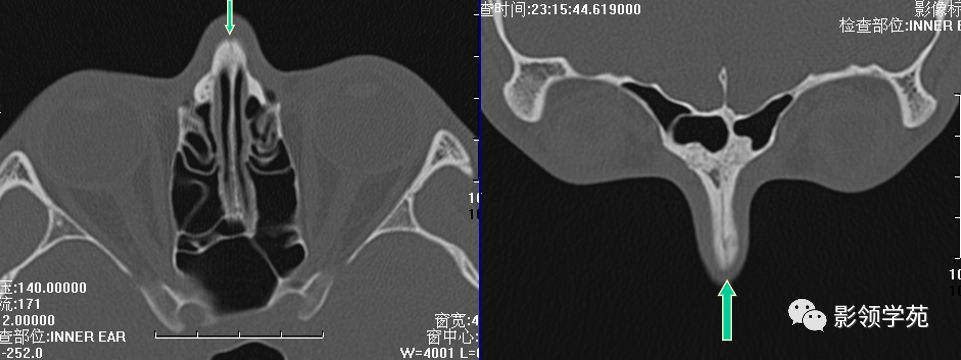

鉴别诊断

- 鼻缝

- 鼻骨孔

- 缝间骨

鼻颌缝

鼻额缝

额颌缝

鼻骨间缝

鼻骨孔

缝间骨